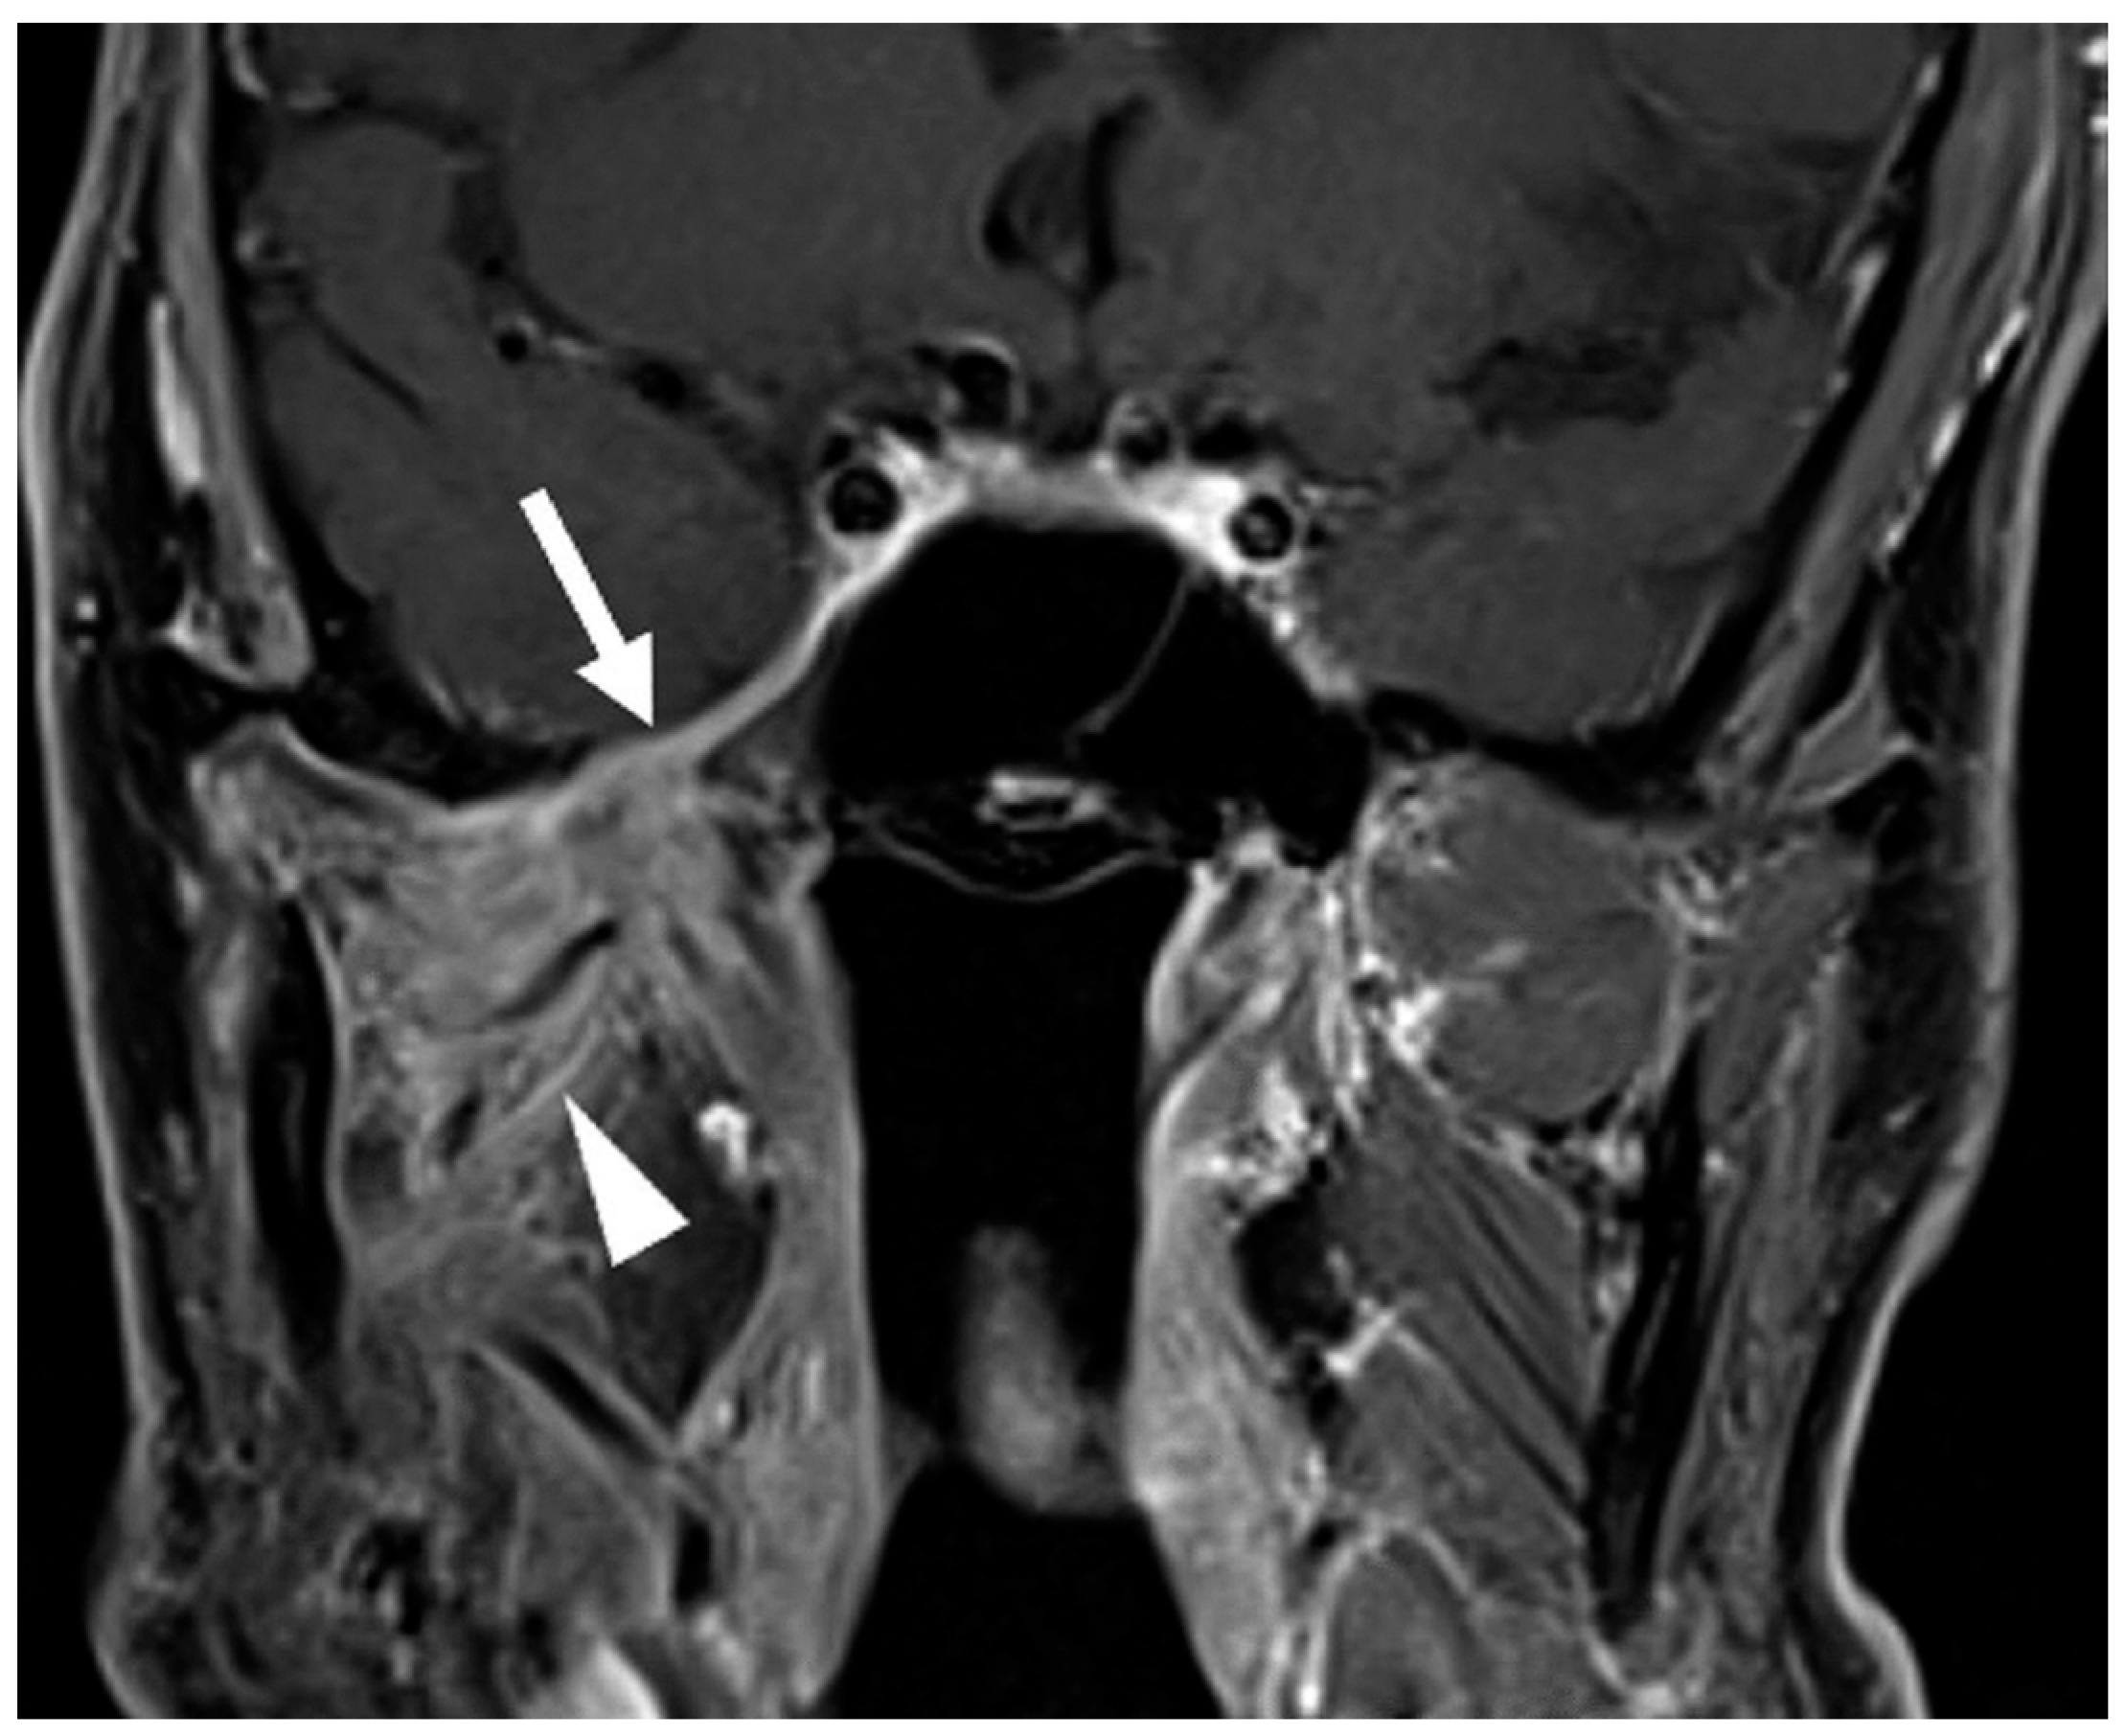

- Overfield, C.J.; Rhyner, P.A.; Hall, M.R.; Bhatt, A.A. More than Skin Deep: Imaging of Dermatologic Disease in the Head and Neck. RadioGraphics 2024, 44, e240052. [Google Scholar] [CrossRef] [PubMed]

- Agarwal, M.; Wangaryattawanich, P.; Rath, T.J. Perineural Tumor Spread in Head and Neck Malignancies. Semin. Roentgenol. 2019, 54, 258–275. [Google Scholar] [CrossRef]

- Majoie, C.B.; Hulsmans, F.-J.H.; Verbeeten, B.; Castelyns, J.A.; Oldenburger, F.; Schouwenburg, P.F.; Bosch, D. Perineural tumor extension along the trigeminal nerve: Magnetic resonance imaging findings. Eur. J. Radiol. 1997, 24, 191–205. [Google Scholar] [CrossRef] [PubMed]